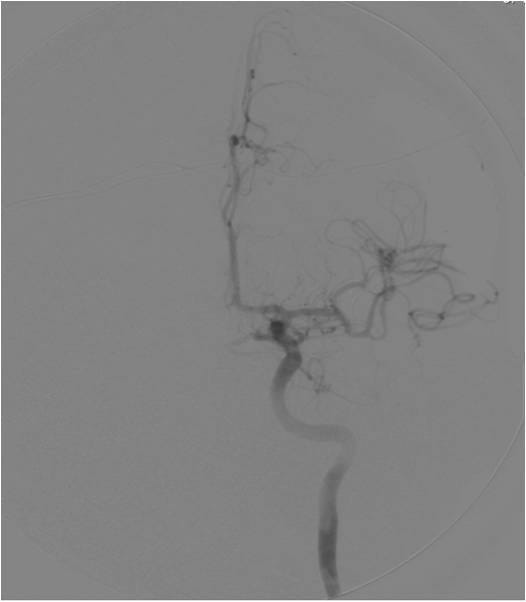

This video documents the surgical clipping of a giant middle cerebral artery aneurysm. The patient is a 56-year-old woman with a Grade I subarachnoid hemorrhage.

Supplemental photos also accompany the video below.